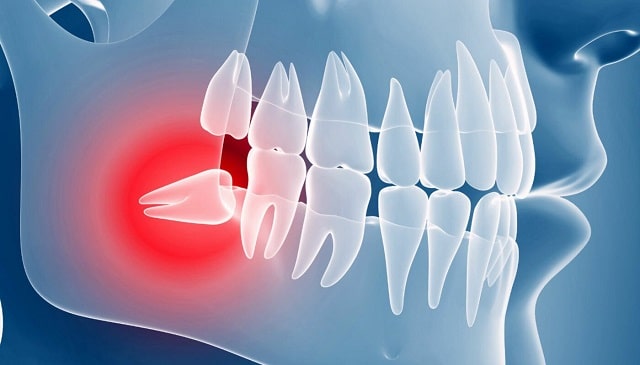

Ретенция зубов — это состояние, при котором зуб полностью сформирован, но не может прорезаться через десну. Такая патология встречается как у детей, так и у взрослых, чаще всего затрагивает зубы мудрости и клыки. Проблема может долгое время оставаться незамеченной, но в запущенных случаях приводит к воспалениям, повреждению соседних зубов и эстетическим дефектам.

Чаще всего ретинированы именно третьи моляры (зубы мудрости), поскольку для них может просто не хватить места в челюсти. На втором месте — клыки, особенно верхние, которые играют важную роль в формировании прикуса.

Визуально ретинированный зуб может быть незаметен. Пациенты чаще жалуются на периодическую боль, отек, ощущение давления или воспаление десны. Важно вовремя провести рентгенографию, чтобы определить точное положение зуба и степень его ретенции.